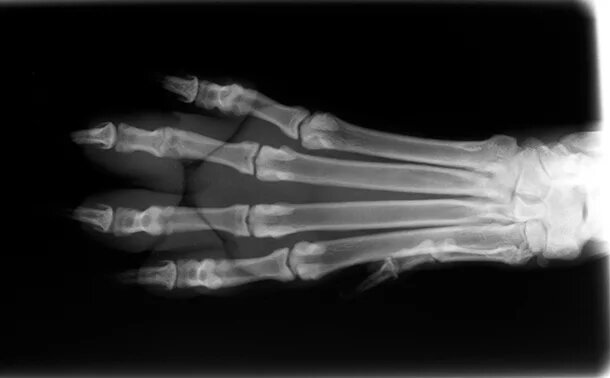

· Рентгенография – основной метод выявления структурных изменений.